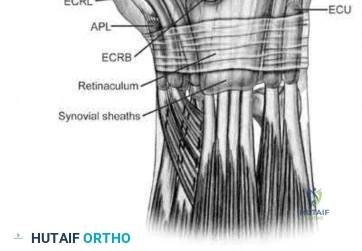

A 55-year-old female underwent non-operative treatment with a short arm cast for a non-displaced distal radius fracture. Eight weeks later, she suddenly cannot actively extend her thumb interphalangeal joint. What is the most common pathophysiologic mechanism for this complication?

Options:

- Iatrogenic laceration from cast removal

- Ischemic necrosis and mechanical attrition of the extensor pollicis longus (EPL) tendon at Lister's tubercle

- Rupture of the extensor pollicis brevis (EPB) tendon

- Posterior interosseous nerve (PIN) entrapment within the fracture callus

- Flexor pollicis longus (FPL) rupture

Correct Answer: Ischemic necrosis and mechanical attrition of the extensor pollicis longus (EPL) tendon at Lister's tubercle

Explanation:

Extensor pollicis longus (EPL) tendon rupture is a classic complication following non-displaced or minimally displaced distal radius fractures. The pathophysiology involves mechanical attrition of the tendon over the fracture callus or roughened bone near Lister's tubercle, compounded by ischemia within the tight intact third extensor compartment due to fracture hematoma and swelling.